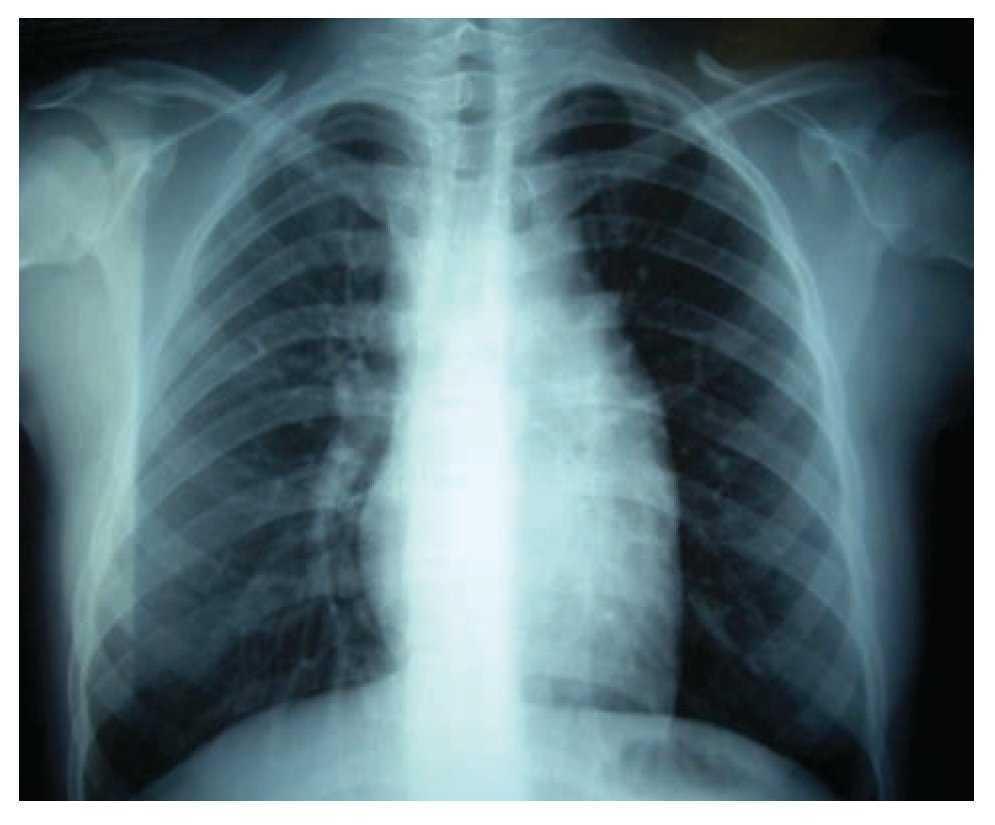

Adolescente femenino de 12 años de edad con antecedentes de cáncer materno en cinco miembros de la familia, con un cuadro de seis meses de evolución con deterioro de su estado general (astenia, adinamia, hiporexia, fiebre vespertina hasta de 380, pérdida de 8 kg de peso) y adenopatías periféricas. En la exploración física se percibe conglomerado ganglionar supraclavicular derecho e izquierdo de 5 cm por 3 cm, red venosa colateral en la cara antero-superior de hemitórax izquierdo, hipoventilación superior izquierda con matidez a la percusión; el resto de la exploración resulta negativa. Los exámenes de laboratorio fueron normales, excepto la velocidad de sedimentación globular 30 mm/60 min. La radiografía de tórax mostró una gran masa en el mediastino (Imagen 1); la tomografía axial computarizada de tórax reveló una imagen lobulada, hiperdensa hacia el parénquima pulmonar, localizada en el mediastino medio, anterior y superior, que desplazaba la silueta cardiaca hacia abajo y hacia el lado izquierdo, la cual mostraba reforzamiento leve cuando se aplicó contraste. Además, comprimía, en su porción posterior, ambos hilios sin obliterarlos; el parénquima pulmonar sin alteraciones (Imagen 2).

Imagen 1. Radiografía simple de tórax, donde se observa una gran masa mediastinal.